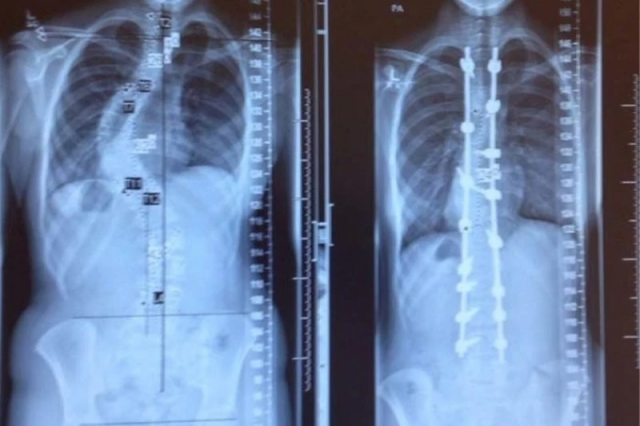

Позвоночник до и после лечения сколиоза. Обычно хирургическое вмешательство и установка конструкции проводится только в том случае, если искривление превышает 50%